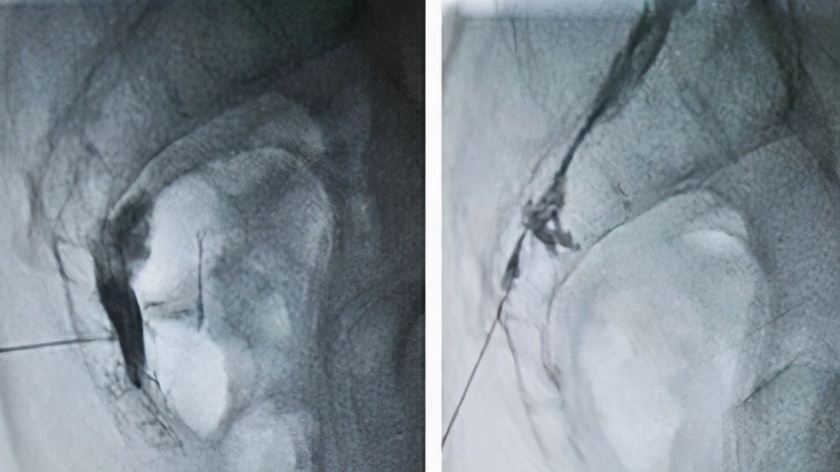

在这里,疼痛科田德民主任及其疼痛科团队给出了明确诊断,并为其详细制定了微创解决方案。仅仅两根穿刺针的治疗后,折磨了楼阿姨3年的疼痛竟神奇般地消失了。术后第三天,楼阿姨心情异常的好,那折磨人的疼痛再也没有出现,对于大小便的恐惧也自然没有了。楼阿姨对效果非常满意,几日后顺利康复出院。

市立医院疼痛科开展的针对支配会阴区疼痛的交感神经和感觉神经的微创治疗已在临床证实对于本病有较高的有效率和优越性。